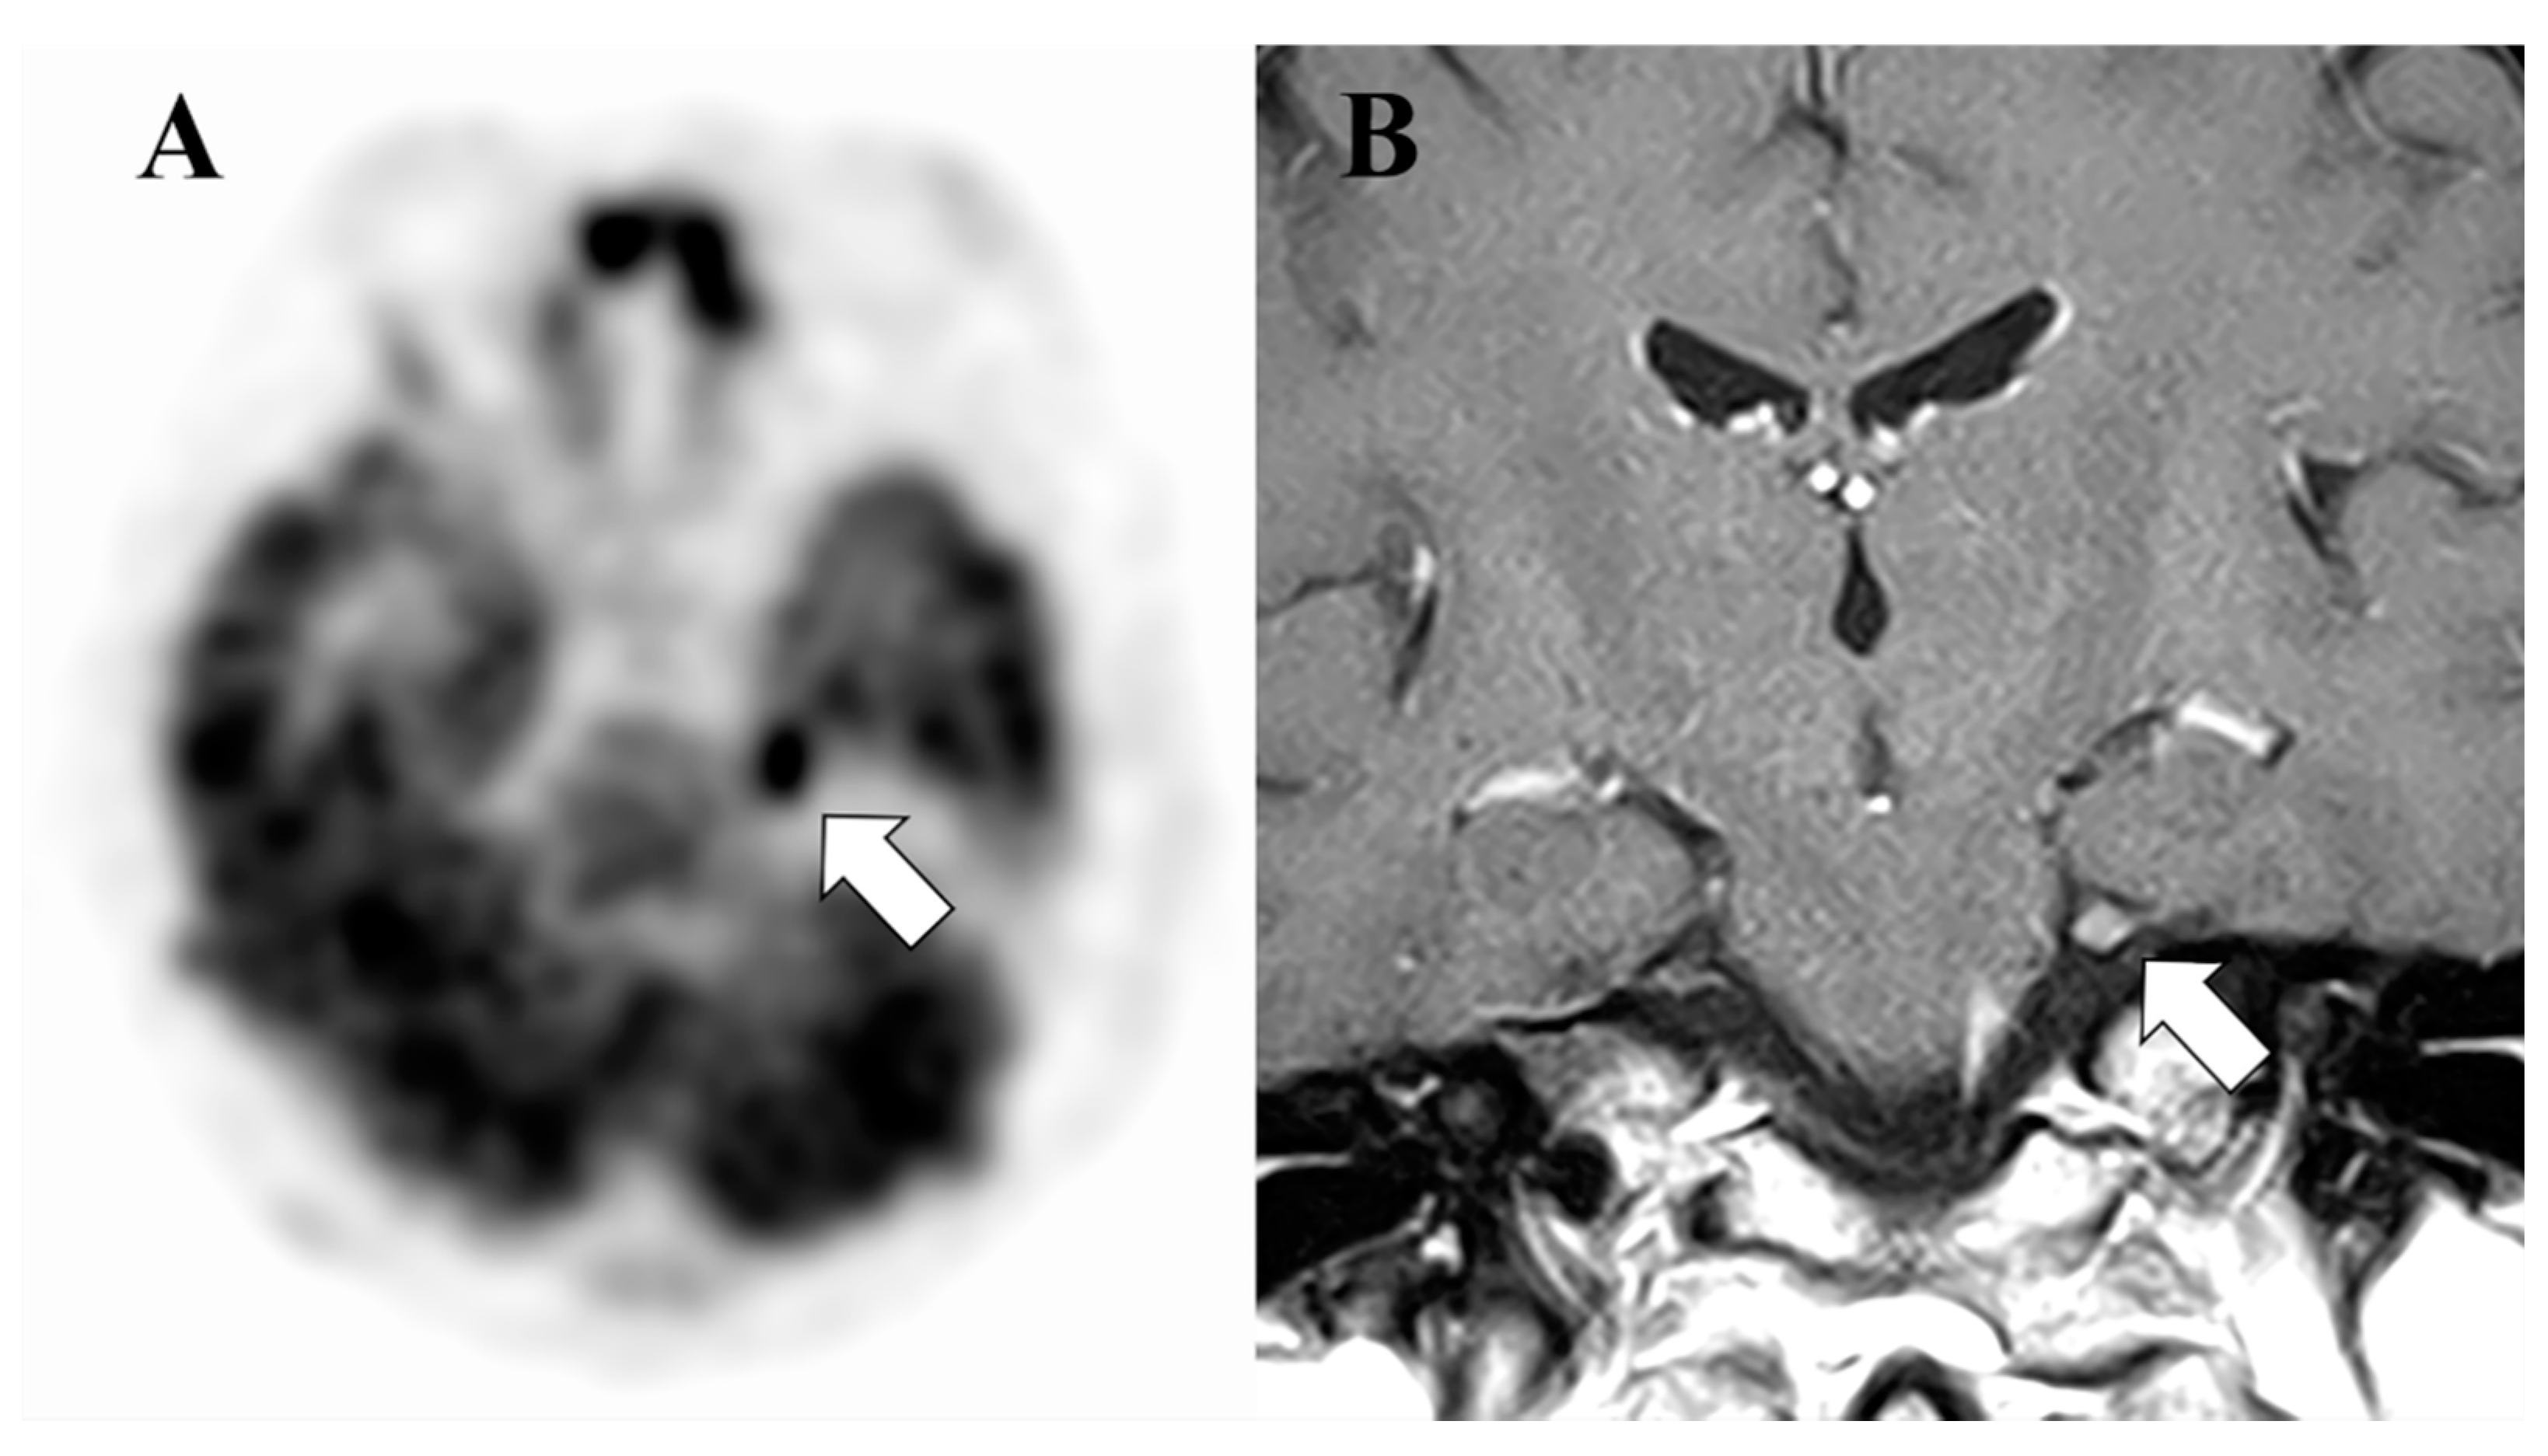

Figure 1.

A 43-year-old female patient with NL. (A). A FDG PET image shows high accumulation in the left trigeminal nerve. (B). A coronal image of contrast enhanced MRI shows thickening and abnormal enhancement of the left trigeminal nerve, which was confirmed to be a true lesion.